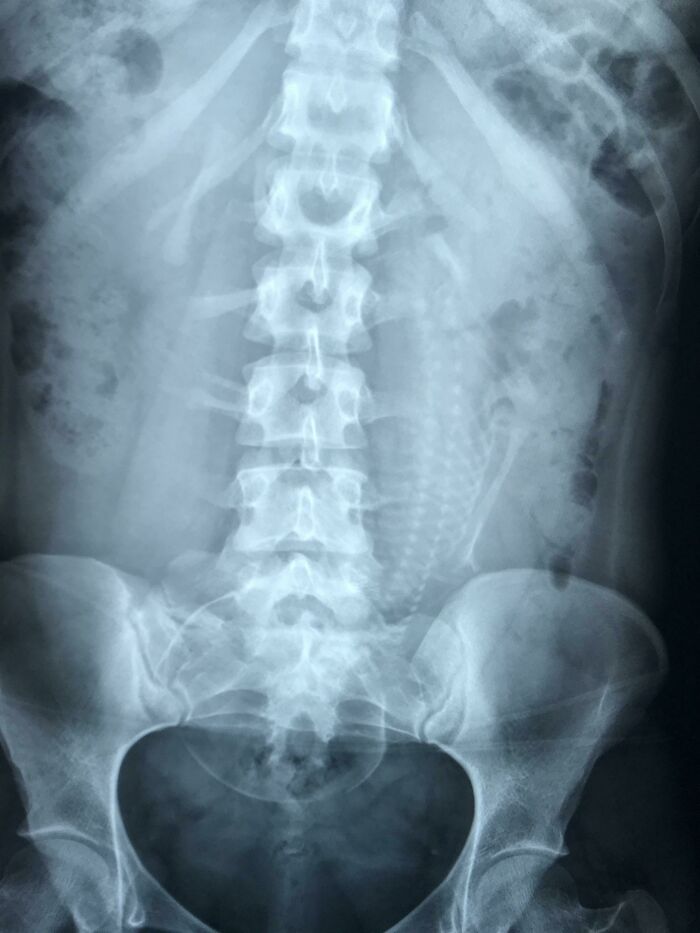

My immune system went after my kidneys. Now I’m on dialysis and hoping to get on the transplant list. They put me on chemo to destroy my immune system just to make it stop so now it takes me forever to heal, if I ever do.